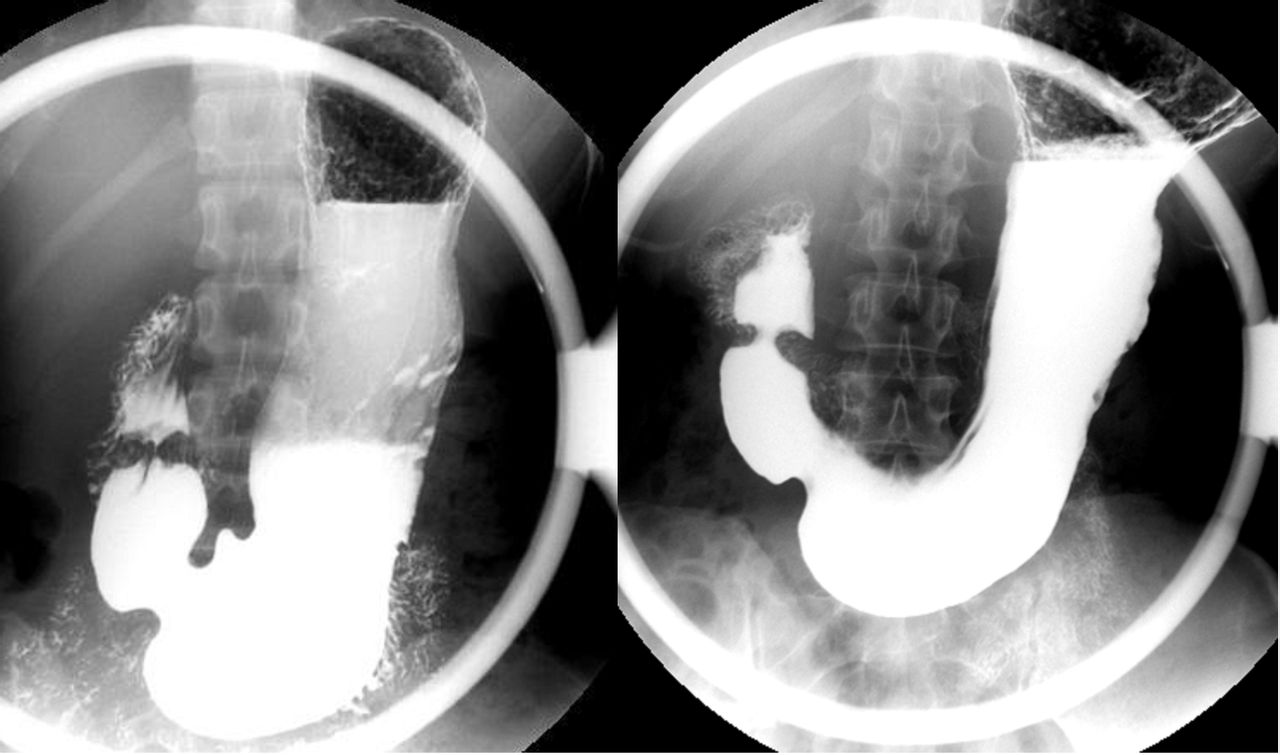

上消化道钡餐造影

钡餐造影

帮忙看看胃钡餐片